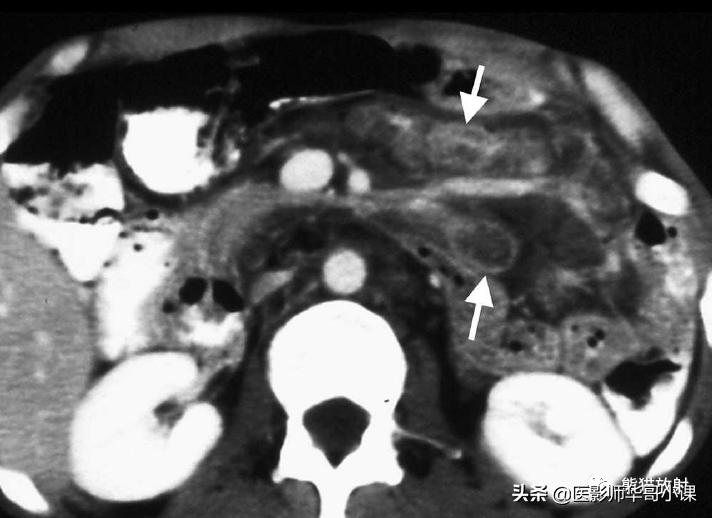

是一种罕见的由革兰阳性杆菌引起的多系统受累的感染性疾病。CT可见小肠壁弥漫性增厚,肠系膜及腹膜后多发肿大淋巴结, 淋巴结密度较低 ,这是由于脂肪和脂肪酸的沉积造成的(图)。

惠普尔病。小肠系膜内可见无强化的低密度淋巴结(箭)